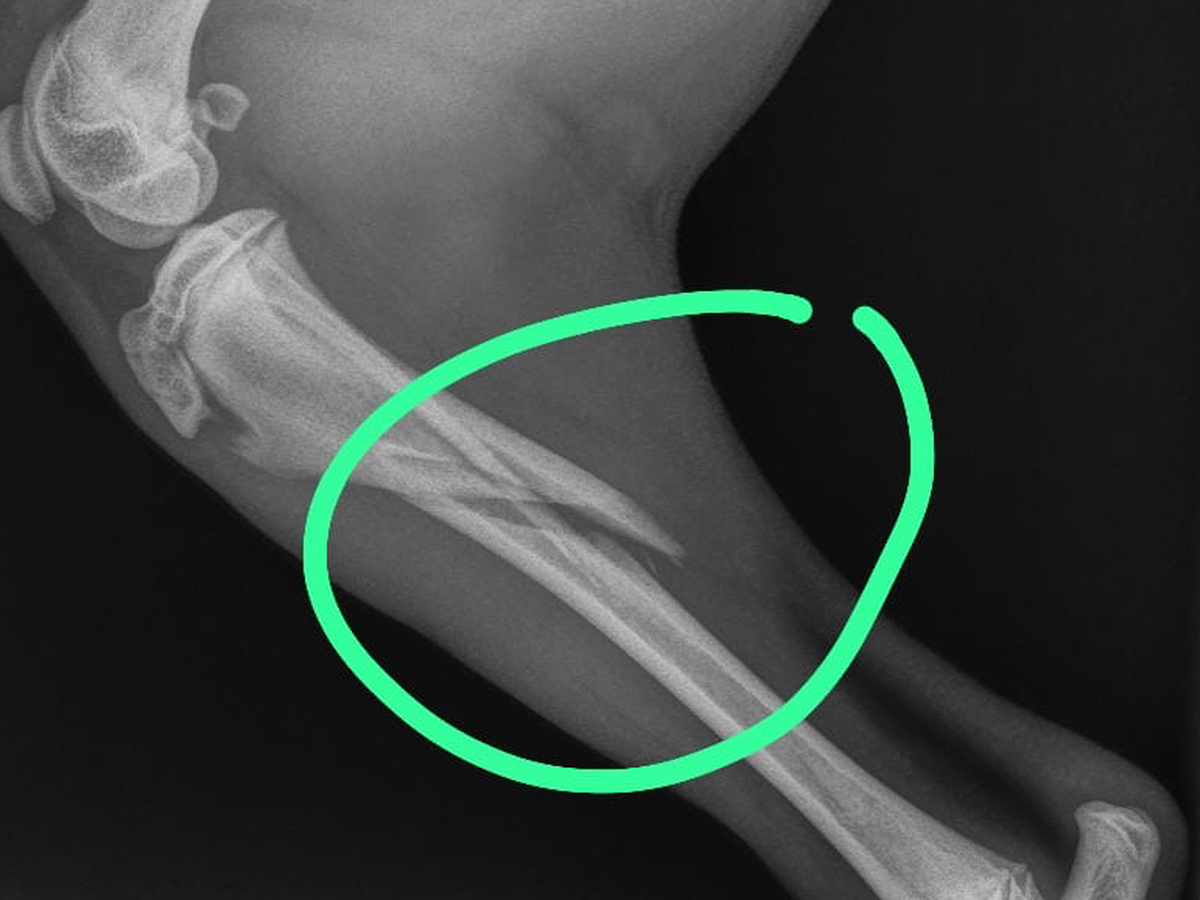

is percy ik zamel geld in voor me lieve kleine pup Bintang hele hoge kosten woord dit poot gebroken ik ken dit niet alleen zo op hoesten ik hoop dat mensen me kunnen helpen